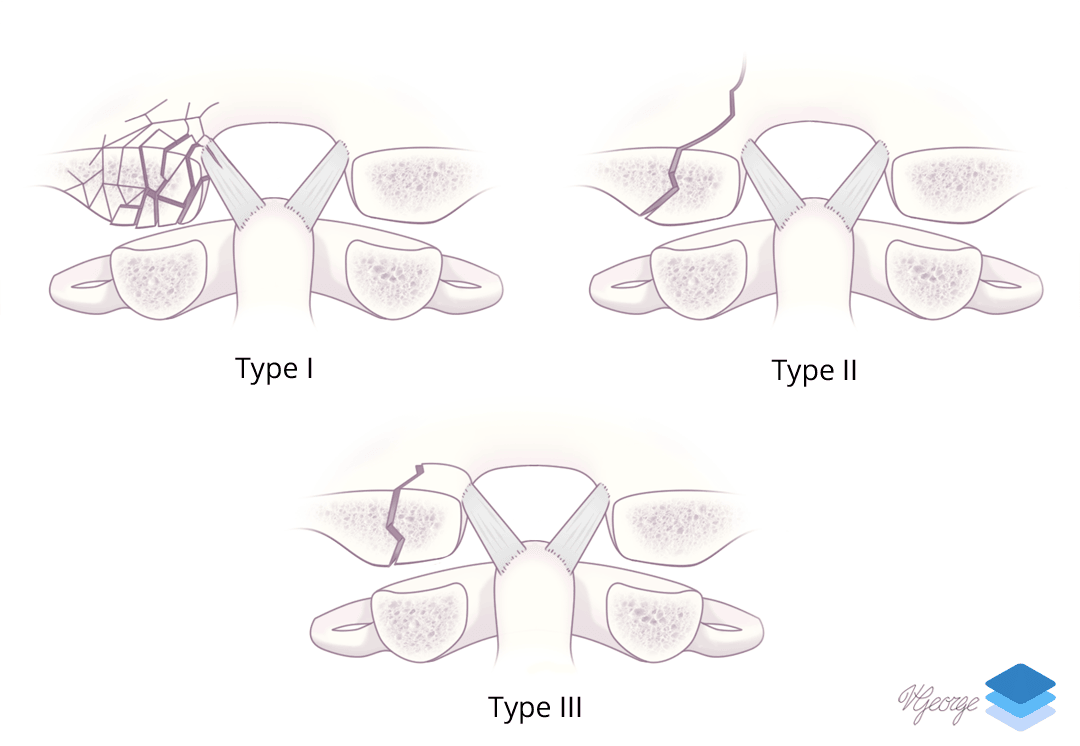

- Remember that the alar ligaments attach to the occipital condyle. Displaced avulsion fractures are considered unstable injuries concerning for underlying ligament injury, and while you do not need to know the surgical classification schemes, make sure to mention whether or not these fractures are displaced

Occipital condyle fractures.